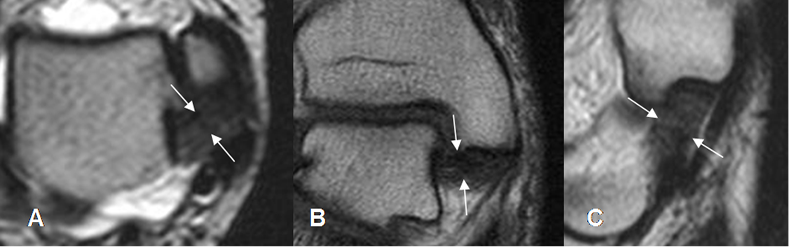

Fig 19. Fascia plantar normal.

A y B: RM axial en T1 y C: RM coronal en T1. Rama medial (Flecha delgada), central (Flecha gruesa) y lateral (Cabeza flecha).

Fig 20. Fascia plantar normal.

A: RM sagital en T2 y B: RM sagital en STIR. Estructura hipointensa en todas las secuencias.